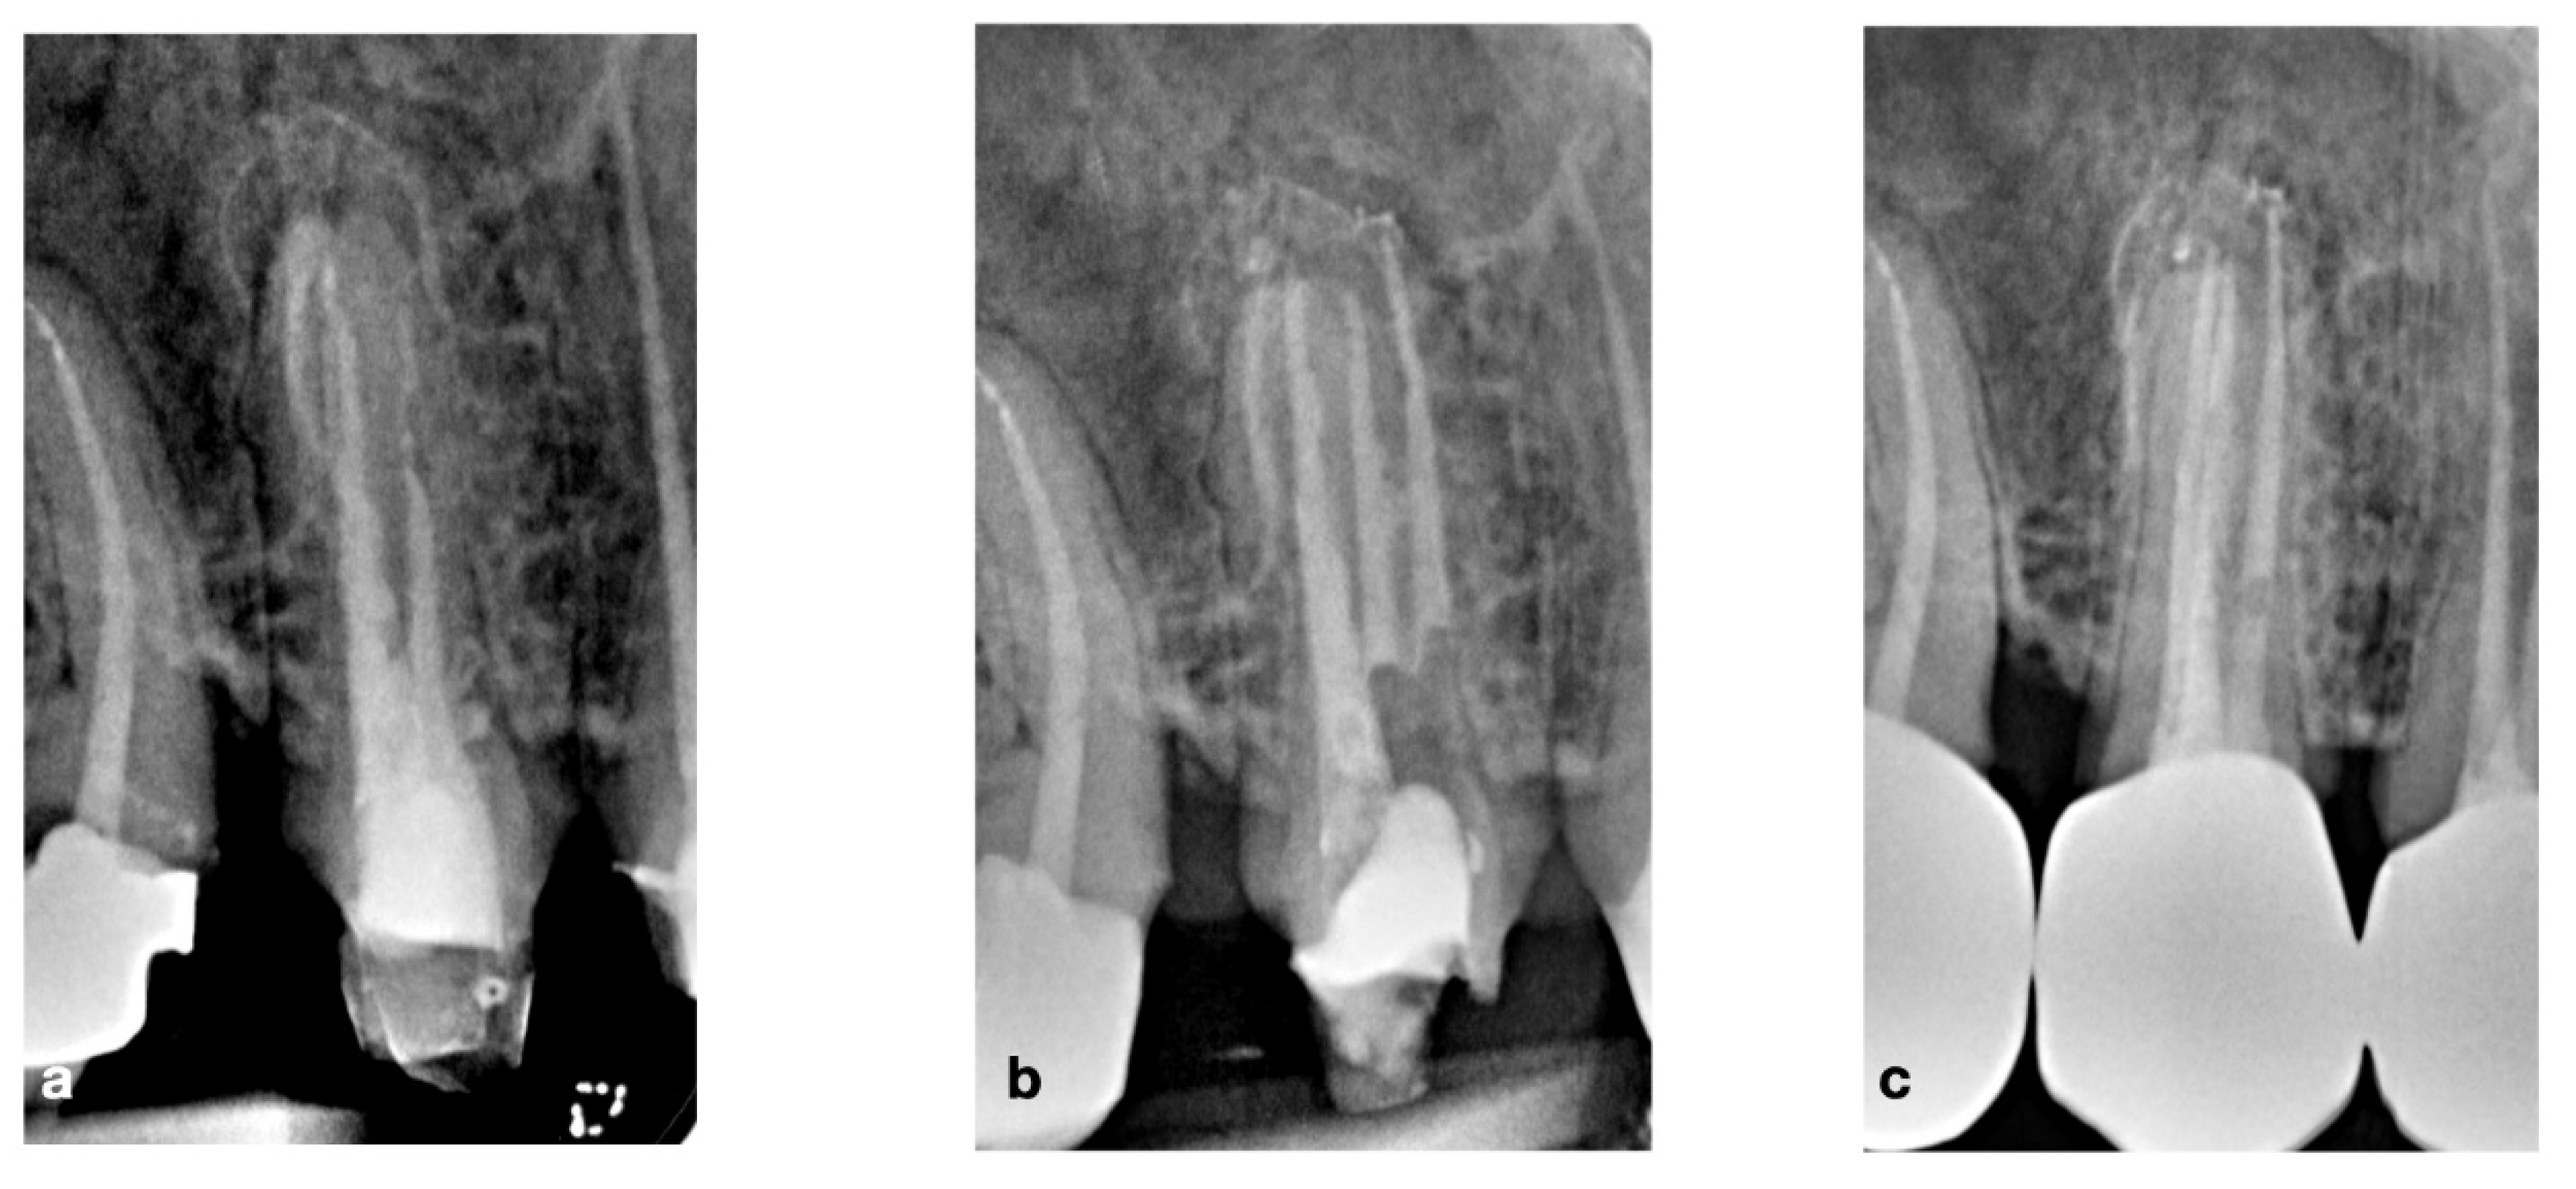

2.4. CASE 4

2.5. CASE 5